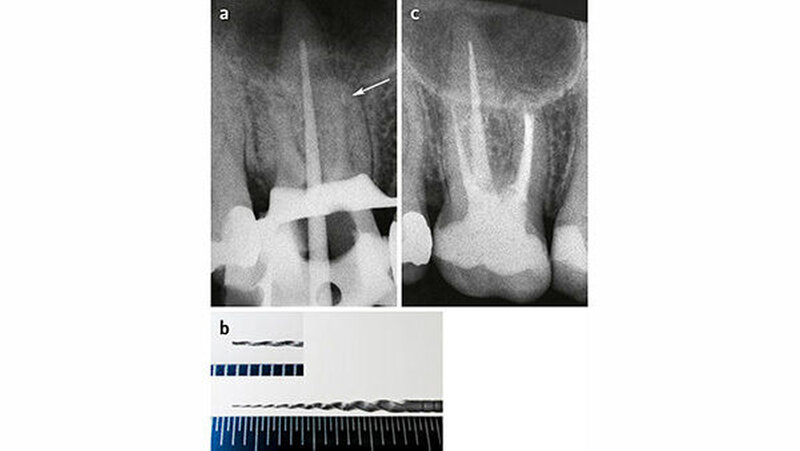

Die langfristige Prognose für einen Zahn nach Instrumentenfraktur ist abhängig vom Grad der Infektion und vom Zeitpunkt der Instrumentenfraktur (Simon et al. 2008; Ungerechts et al. 2014). Je später die Fraktur passiert, desto größer die Wahrscheinlichkeit, dass der Kanal chemomechanisch schon gut aufbereitet ist und demzufolge weniger Mikroorganismen und/oder nekrotisches Gewebe vorhanden sind (Abb. 3). Je fortgeschrittener die Infektion (entzündete Pulpa, nekrotische Pulpa, periradikuläre Aufhellung), desto mehr und tiefer im Kanal liegende Mikroorganismen sind zu erwarten. Außerdem sind bei Revisionen tendenziell resistentere Keime zu erwarten als bei Ersteingriffen.